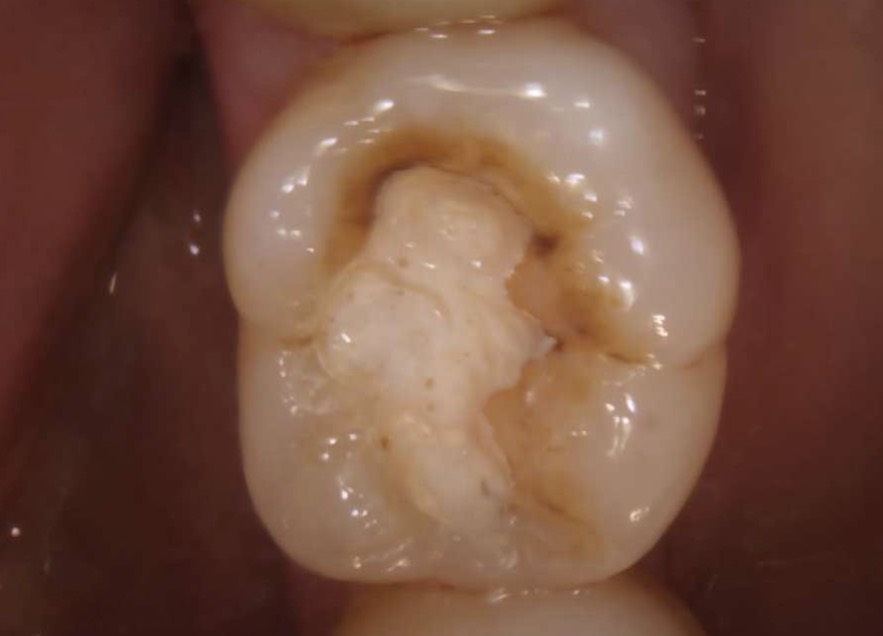

| 主訴 | 左下の奥歯の銀歯が取れた。 |

|---|---|

| 所見 | 下顎左側第一大臼歯咬合面二次う蝕 |

| 診断 | 下顎左側第一大臼歯咬合面う蝕1度 |

| 治療内容 | コンポジットレジン修復 |

| 治療後経過 | 痛みなく、咬合状態も良好。 |

| 治療期間 | 1回 |

| 治療費用 | 保険診療一本で1500円程度。 |

| リスク・副作用 | 今後も材料の経年劣化によって摩耗による着色や破折する可能性があると伝えた。 |